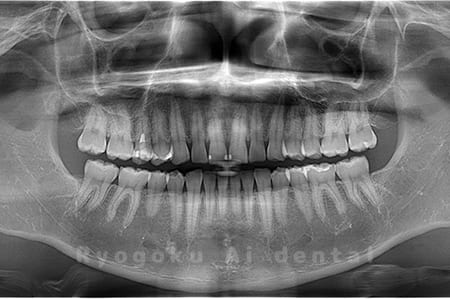

Case03

-

- 原因

- 上顎、下顎の親知らず

- 治療内容

- 上下4本の親知らずを抜歯したケースです。

<リスク・副作用>

手術後は痛み、腫れ、痺れなどの副作用が生じる場合があります。